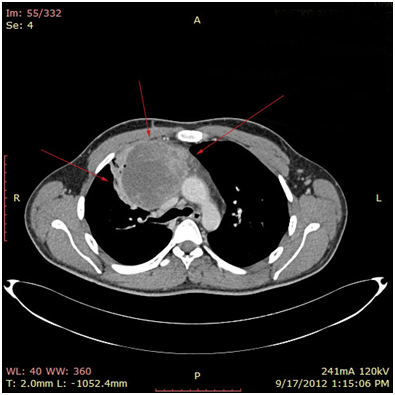

The 1st case we report is of a 22-year-old Caucasian male, who was admitted to our hospital with a 3-days history of progressive dyspnea on exertion, neck swelling, fatigue, persistent chest pain, pyrexia, and a cough that was occasionally productive of blood. The physical examination revealed a heart rate of 115 beats per minute (Sinus Rhythm), a respiratory rate of 25 breaths per minute and superficial vascular distention over the neck. Laboratory studies revealed elevated serum α-fetoprotein (AFP) (5380 IU/ml) and D-dimer (481ng/ml). A chest X-ray in the poster - anterior view, upon admission, depicted a suggestive right upper mediastinal mass (Bild 1). Radiography was followed by contrast-enhanced CT scan that revealed a large, homogeneous mediastinal mass crossing into the anterior mediastinum and compressing – encasing the superior vena cava. It also showed signs of thrombosis of the left brachiocephalic vein, and multiple filling defects at the left pulmonary artery indicating embolism. Subcarinal lymphadenopathy, as well as enlarged lymph nodes of the right hilum was present (Bild’s 2-5). On median sternotomy, a large non resectable tumor was observed involving the in nominate vein and the superior vena cava (Bild 6). Great care was taken to remove as much tumor mass as possible. To decompress the superior vena cava, we had to perform an extensive resection and reconstruction of the cephalad part of the superior vena cava using homolog pericardium.A histopathological examination of a section of the mass revealed a mixed NSGCT (embryonal yolk sac/endodermal sinus tumour), containing also elements of embryonal carcinoma (Figure 1-6).The patient was placed on cisplatin-based chemotherapy (BEP regimen: cisplatin 50mg/m2 on days 1-2, etoposide 165mg/m2 on days 1-3, bleomycin 30U on days 1, 8, and 15, every 3 weeks). Tumor markers were elevated for a-FP (214ng/mL) and normal for β-HCG. The patient completed 4 cycles of chemotherapy and the subsequent chest CT (Bild 7) revealed a partial remission of the mass (decrease>50% of the size). The a-FP was normal as well as the β-HCG. The remaining mass was inoperable so the patient was started on salvage chemotherapy with the TIP (paclitaxel, ifosfamide, ciplatin) regimen for 4 cycles. The post-chemo chest CT showed stable disease and the patient was referred to radiation oncologists for radiotherapy of the remaining tumor. Three months later af P was found elevated and the CTs revealed multiple brain metastases. Whole brain radiation was performed and the patient was placed on gemcitabine (d1 and d8 every 21 days). Two months later the neurologic status deteriorated with new brain metastases and the patient passed away (19 months after the diagnosis).

Bild 2 CT – axial plan of a large Yolk sac tumor in the anterior mediastinum invading the art. Carotis communis. White arrow pointing low attenuation foci, suggesting central necrosis.

Bild 4 CT – axial plan demonstrating a 10cm Yolk sac tumor invading the truncus pulmonalis and the vena cava superior.